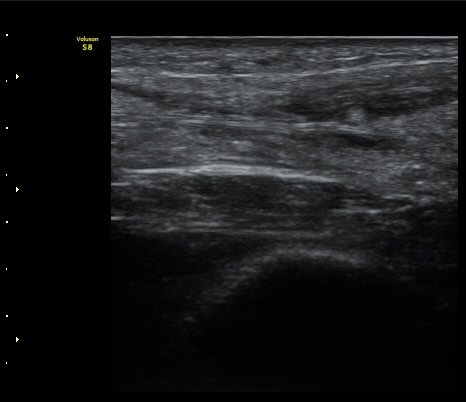

[¹ß¸ñ] ¾ÆÅ³·¹½º ÈûÁÙ ÆÄ¿­ÀÇ ÃÊÀ½ÆÄ Áø´Ü

ÁÂÃø ¹ß¸ñÀÇ ÅëÁõ(2ÁÖ)

2ÁÖ Àü ¹èµå¹ÎÅÏÇÏ´Ù°¡ ¹ß¸ñÀÇ ÅëÁõÀÌ ¹ß»ýÇÏ¿© Ÿº´¿ø¿¡¼­ ÃÊÀ½ÆÄ°Ë»ç µî ½ÃÇàÇÏ°í ºÎ¸ñ°íÁ¤ ÈÄ ¹°¸®Ä¡·á À§ÇØ ³»¿ø

¾ÆÅ³·¹½º°Ç ºÎÁ¾ ¹× ¾ÐÅë, ´Éµ¿Àû ¹ß¸ñ ¹ß¹Ù´ÚÃø ±¼°ñ G 1, thomson test(+).

ÃÊÀ½ÆÄ °Ë»ç